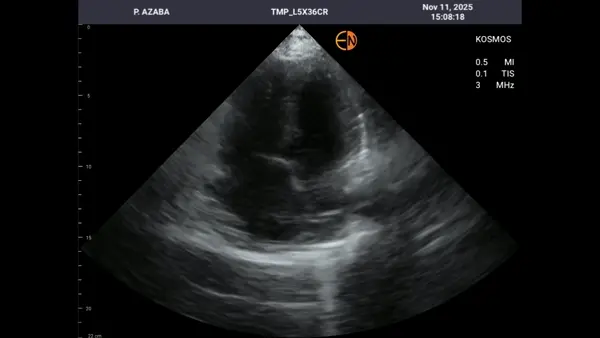

A 89-year-old man with congestive heart failure and a TAVI performed four months earlier presented with shortness of breath and desaturation. A bedside AISAP exam revealed EF 18%, severe MR, severe TR, and an enlarged right atrium.A formal echocardiogram confirmed these findings, and he was referred for MitraClip as part of his comprehensive management plan.